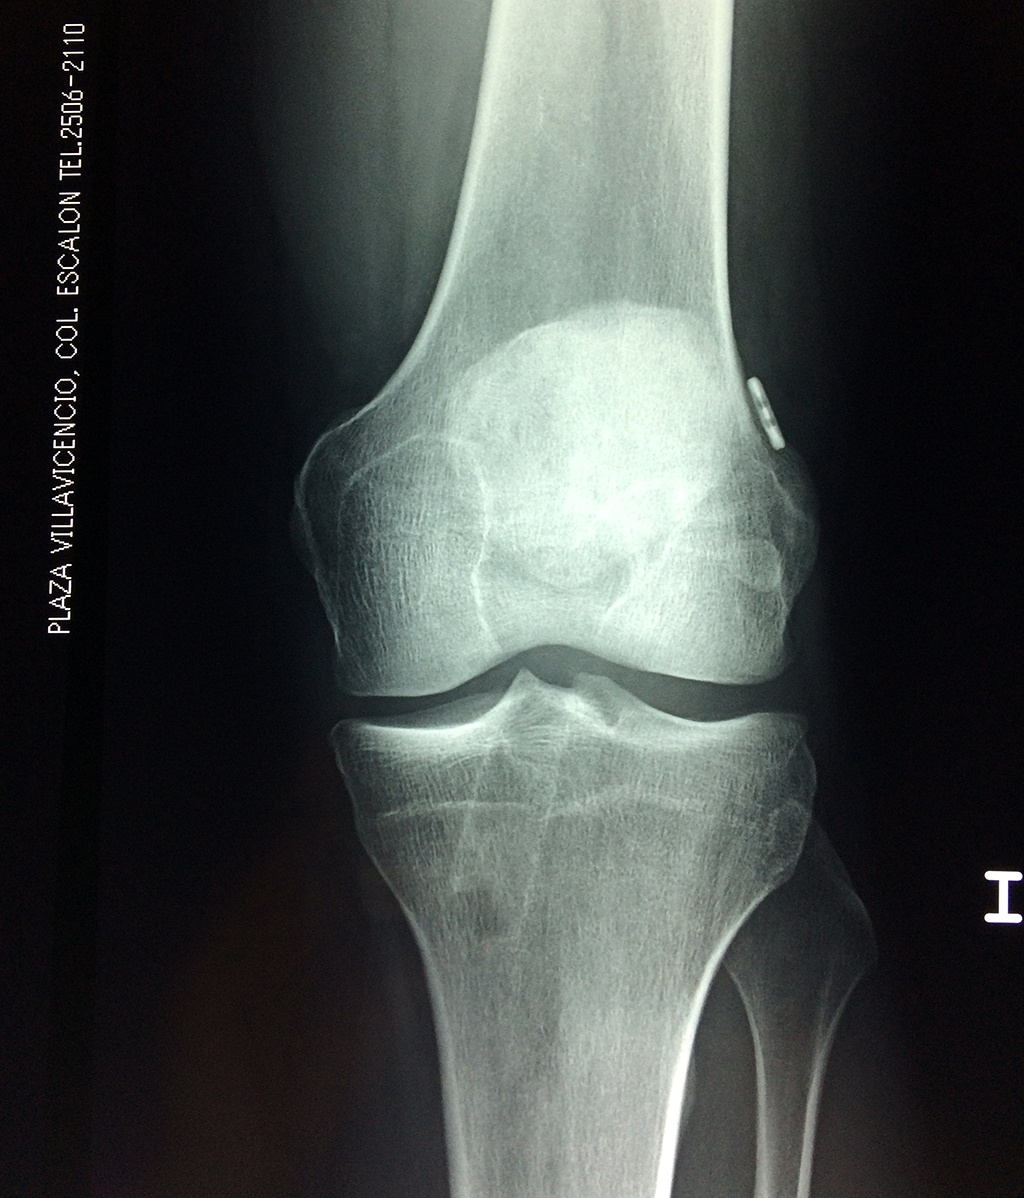

Cirugías de Rodillas